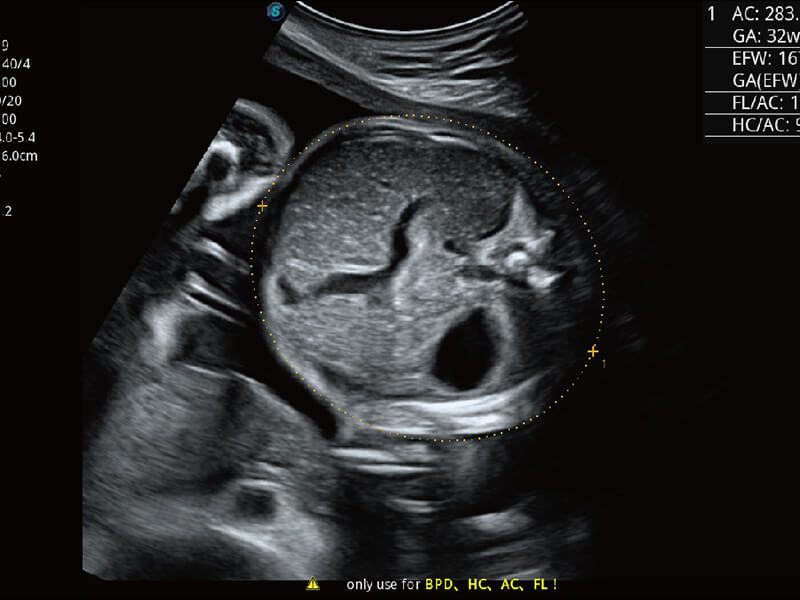

S-Fetus 产科扫查助手

• 缩短

操作时间

• 提升

准确率

• 单次

按键操作

高分辨率容积成像 栩栩如生

超宽频带技术,为容积成像带来优质的二维图像基础,为您呈现丰富的结构细节,栩栩如生地展示宝宝的宫内形态以及各种组织的立体结构。